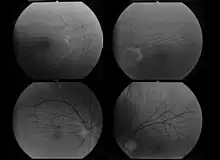

A diagnosis of far-sightedness is made by utilizing either a retinoscope or an automated refractor-objective refraction; or trial lenses in a trial frame or a phoropter to obtain a subjective examination. Ancillary tests for abnormal structures and physiology can be made via a slit lamp test, which examines the cornea, conjunctiva, anterior chamber, and iris.[10][11]